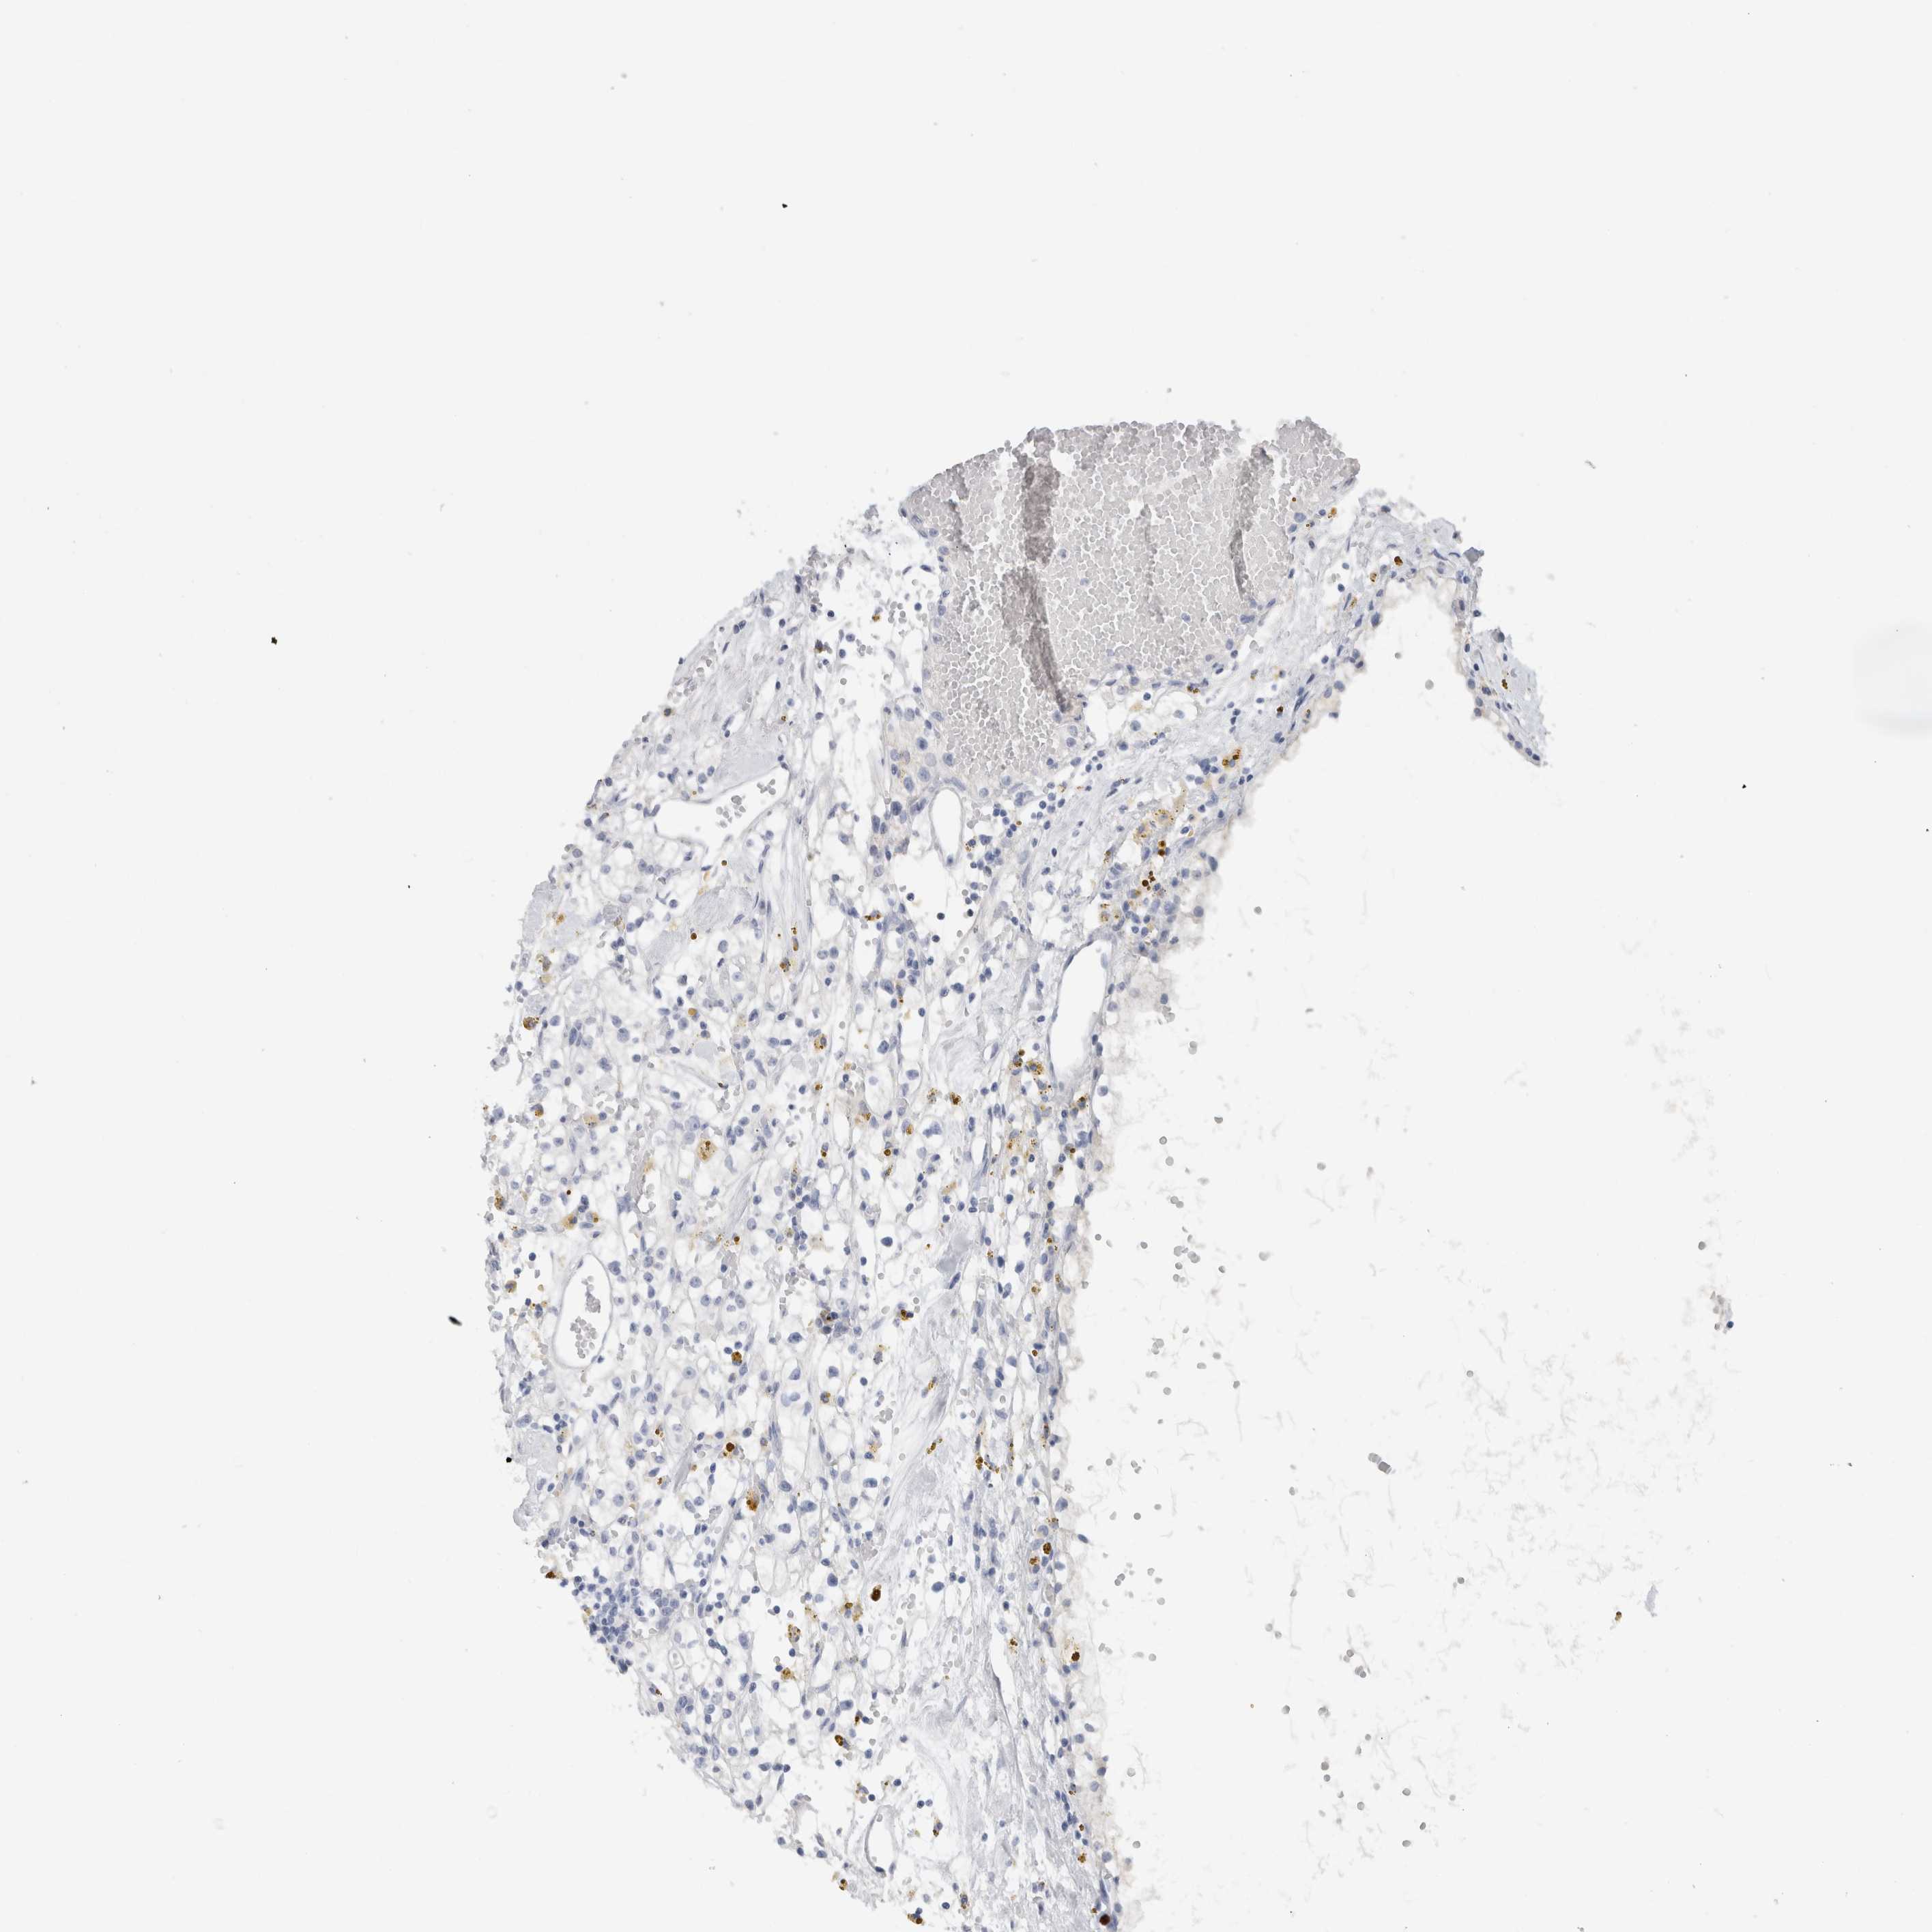

CANCER RENAL CANCER Show tissue menu

KICH TCGA KIRC TCGA KIRC VALIDATION KIRP TCGA PROTEIN RCC CPTAC PROTEIN EXPRESSION

BCAN is not prognostic in Kidney Renal Papillary Cell Carcinoma (TCGA)